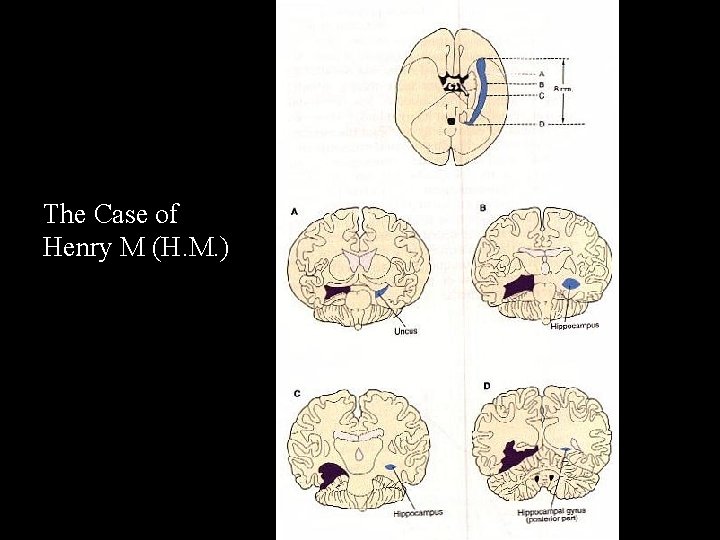

The Case of Henry M (H. M. )